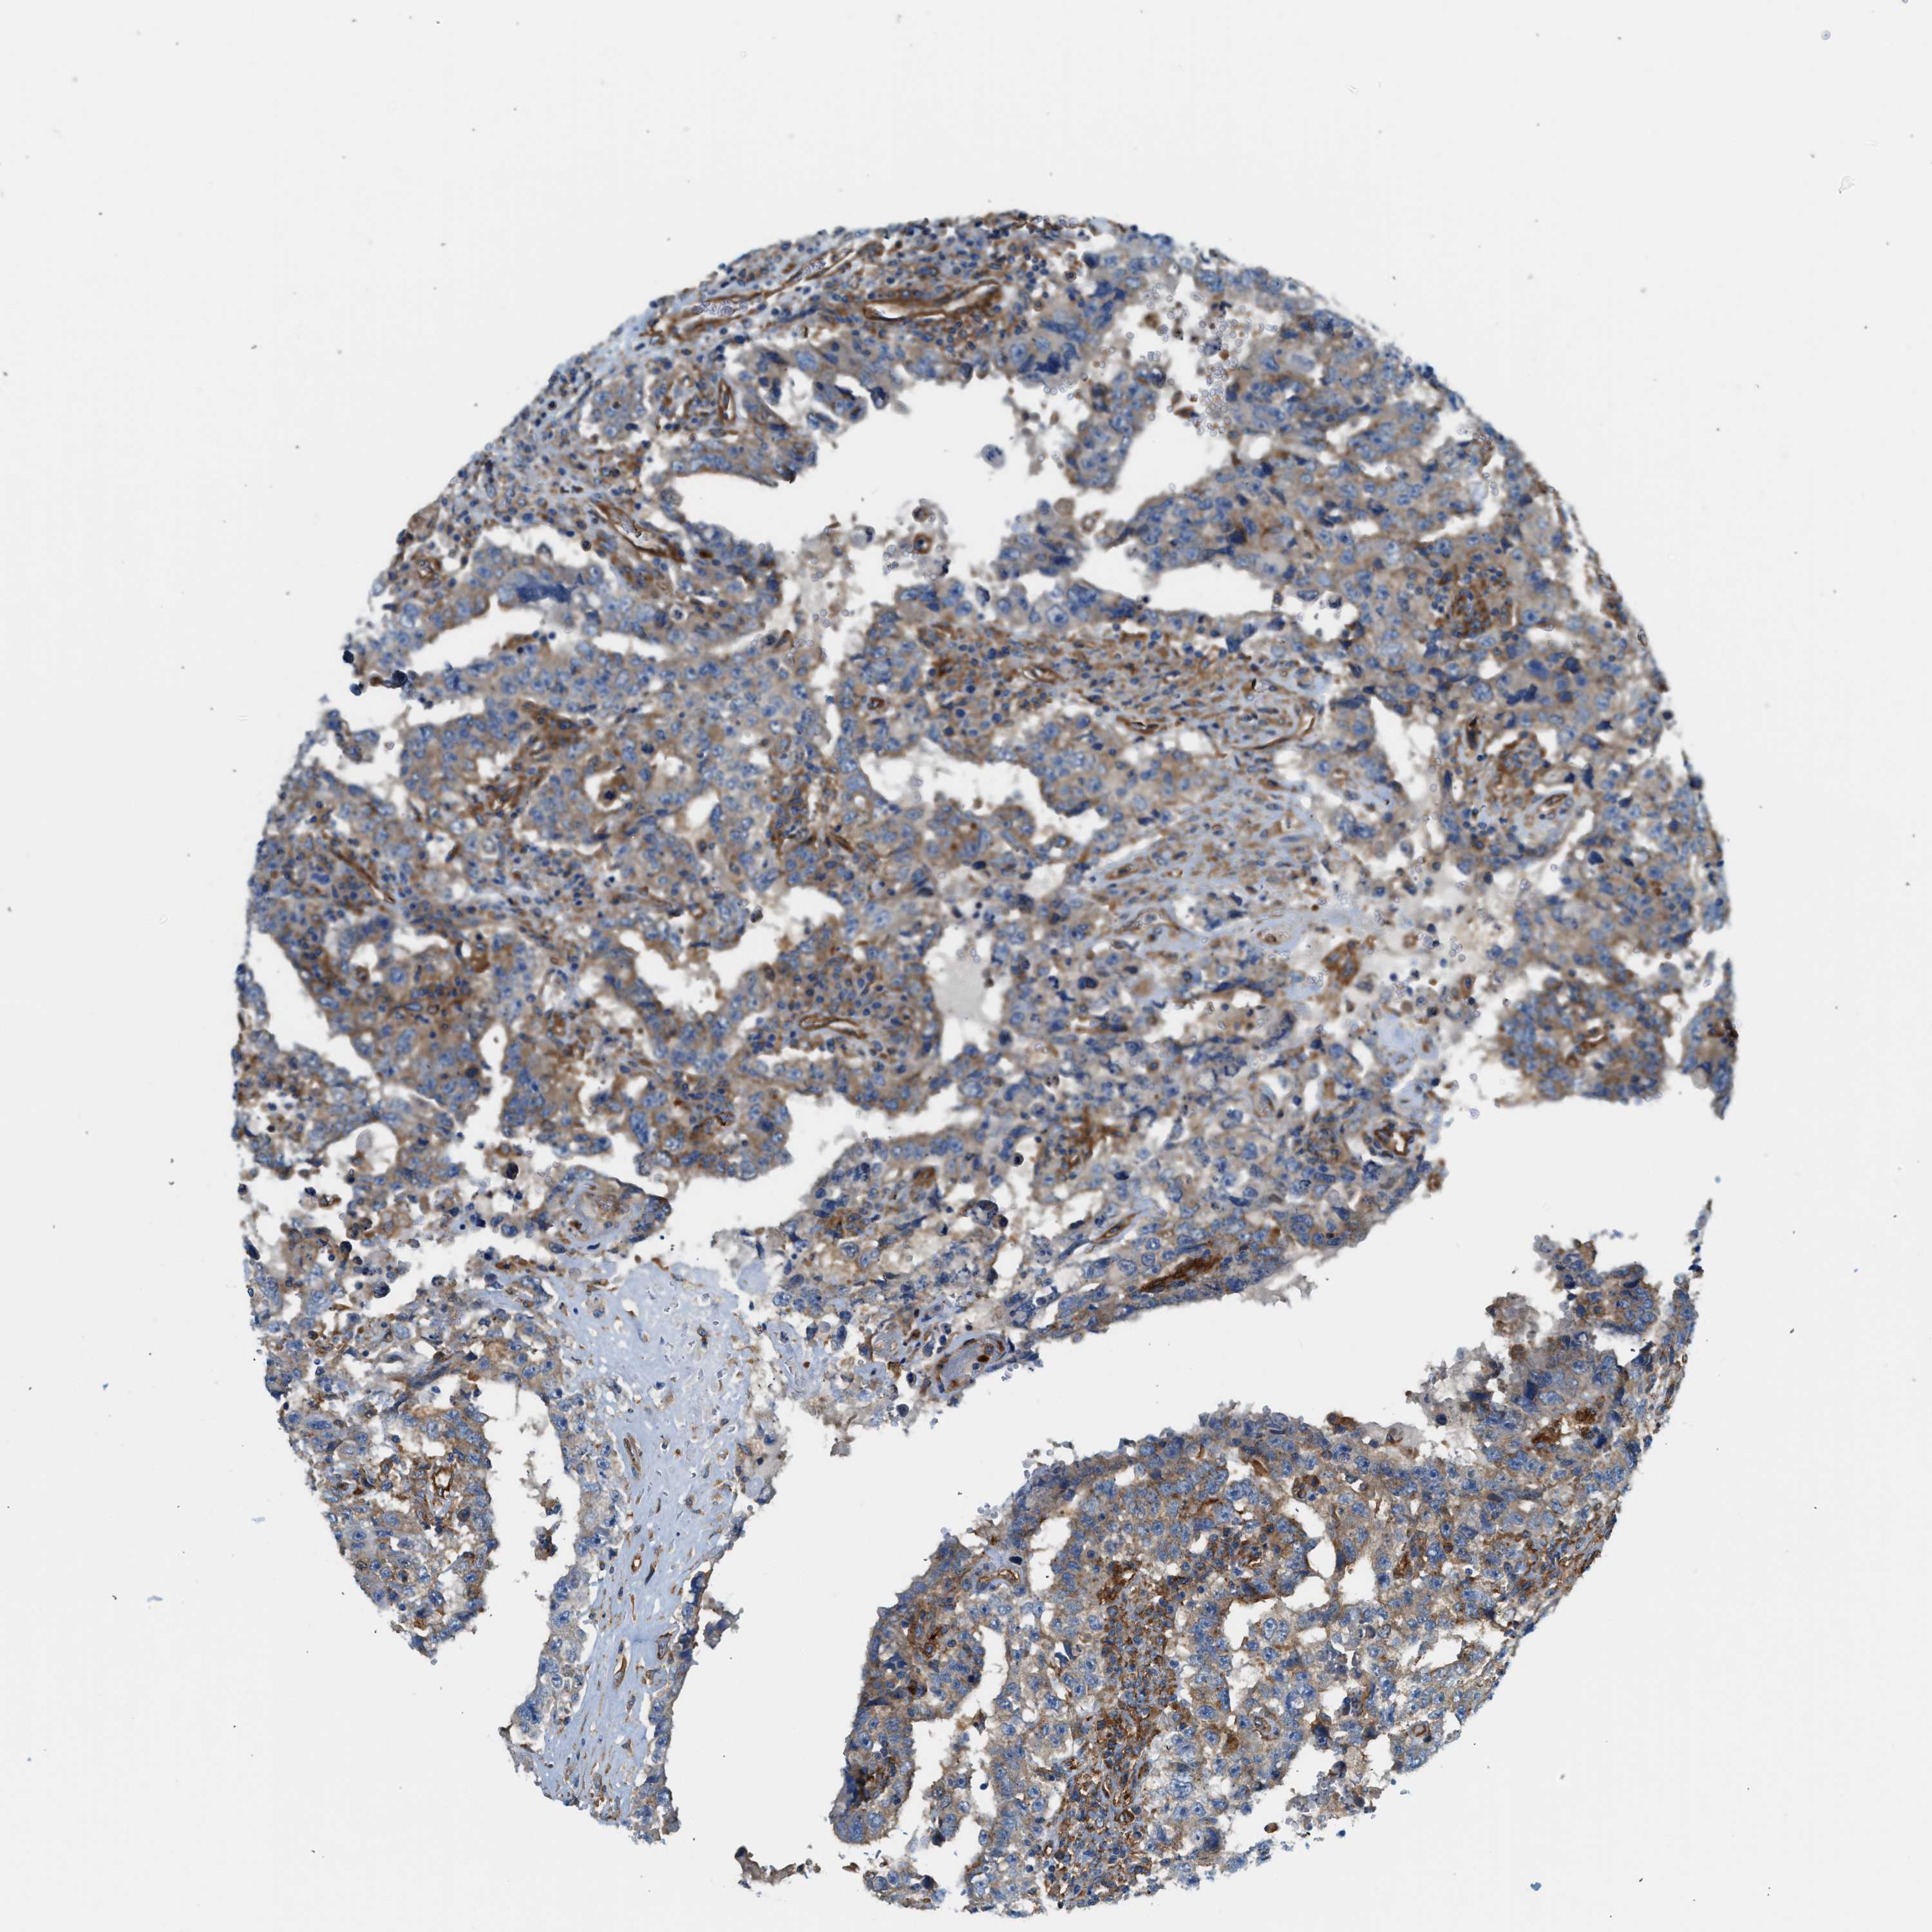

TESTIS CANCER - Protein expressioni

A mouse-over function shows sample information and annotation data. Click on an image to view it in a full screen mode. Samples can be filtered based on level of antibody staining by selecting one or several of the following categories: high, medium, low and not detected. The assay and annotation is described here.

Note that samples used for immunohistochemistry by the Human Protein Atlas do not correspond to samples in the TCGA dataset.

Antibody stainingi

Antibody staining in the annotated cell types in the current human tissue is reported as not detected, low, medium, or high, based on conventional immunohistochemistry profiling in selected tissues. This score is based on the combination of the staining intensity and fraction of stained cells.

Each image is clickable and will lead to virtual microscopy that enables deeper exploration of all samples and also displays staining intensity scores, fraction scores and subcellular localization as well as patient and tissue information for each sample.

Antibody HPA017964

Antibody CAB015334

Antibody CAB016402

Carcinoma, Embryonal, NOS

Seminoma, NOS